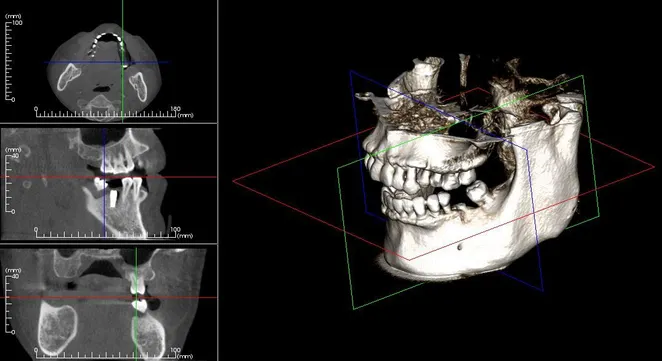

Cone Bean Computer Assembled Tomography

Our office uses the most advanced technology to treat our patients in the most effective way. We use the award-winning i-CAT 3D FLX Cone Beam Computer Assembled Tomography (CBCT) imagining system to acquire the most diagnostic image with less radiation than the average panoramic or traditional x-ray. The dose from this imaging system is 80-95% less than a medical Computed Tomography. With an extremely short scan, typically within five seconds, we can obtain enough data for a comprehensive diagnosis.

i-CAT 3D imaging provides exceedingly beneficial information about the following:

• 3D image system

• Precise location of impacted teeth

• Precise measurement of implant placement

• Bone loss visualization